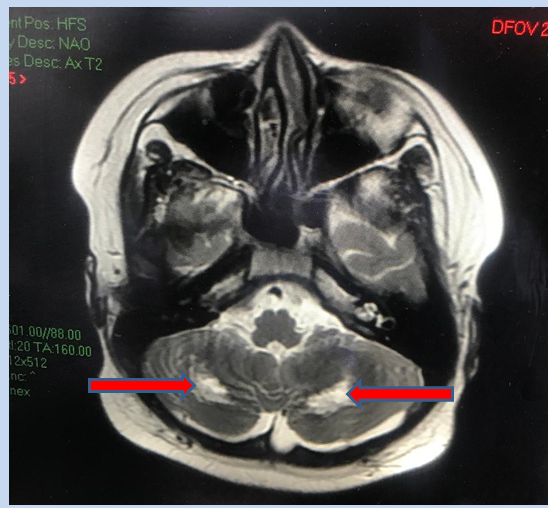

Hình ảnh cộng hưởng từ nhân (MRI) não cho thấy tổn thương chất trắng vùng tiểu não 2 bên gây hiện rối loạn phối hợp vận động, loạng choạng, thất điều.

Trẻ được chẩn đoán sốc nhiễm trùng, nhiễm trùng huyết, viêm phổi nặng, tồn thương gan, COVID-19 N6, được điều trị hỗ trợ hô hấp, kháng viêm, kháng virus, kháng sinh, kháng đông, bù bicarbonate, điều chỉnh điện giải. Diến tiến sau điều trị gần 2 tuần tình trạng trẻ cải thiện dần, các chỉ số viêm cải thiện, xét nghiệm Real Time RT PCR SARS-CoV-2 âm tính. Tuy nhiên đến tuần thứ 3 trẻ sốt lại, đỏ mắt, đỏ da, có biểu hiện rối loạn phối hợp vận động, loạng choạng, thất điều, than nhức đầu, xét nghiệm phản ứng viêm trong máu tăng cao trở lại (VS, CRP, PCT, LDH, Ferritin,…), trẻ được chọc dò dịch não tủy xét nghiệm bình thường và được chụp MRI não, ghi nhận tổn thương đồi thị hai bên, tổn thương chất trắng của tiểu não. Trẻ được chẩn đoán hội chứng viêm đa hệ thống, tổn thương não, được điều trị kháng viêm liều cao, kháng đông phòng ngừa tắc mạch. Kết quả sau thêm một tuần điều trị trẻ hết sốt, hết đỏ da, tỉnh táo, ăn uống khá, xét nghiệm phản ứng viêm về bình thường, được xuất viện điều trị tiếp đủ liệu trình kháng viêm và tái khám theo hẹn.